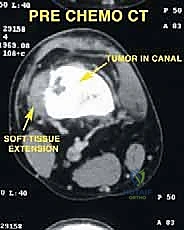

- التصوير بالرنين المغناطيسي (MRI): لتحديد الامتداد الدقيق للورم داخل العظم وفي الأنسجة الرخوة المحيطة (العضلات، الأوعية الدموية).

- التصوير المقطعي المحوسب (CT Scan): لتقييم التدمير العظمي والتخطيط للأبعاد الدقيقة للطرف الاصطناعي المطلوب.

معرض الحالات الإشعاعية: توثيق النجاح الطبي مع د. محمد هطيف

الصور الإشعاعية قبل وبعد الجراحة هي الدليل القاطع على دقة ونجاح الإجراء الطبي. نستعرض هنا مجموعة من الصور التي توضح حجم الإنجاز الطبي في استبدال العظم المصاب بمفصل معدني متطور.